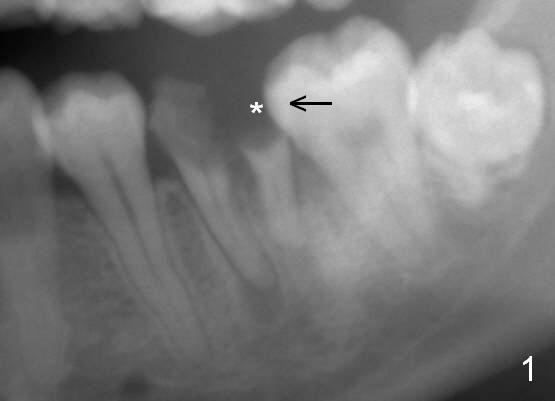

A 29-year-old man presented for #19 extraction a year ago (Fig.1). Probably due to long-termed loss of the distal portion of the crown of #19 (*), the tooth #18 has undergone mesial tilting (arrow). Now he returns requesting implant, but the tilting is worse (Fig.2 double arrows). What X-ray cannot show is severe atrophy buccolingually, increasing difficulty in implant placement. A much smaller implant can be placed (Fig.3), as compared to an immediate implant.